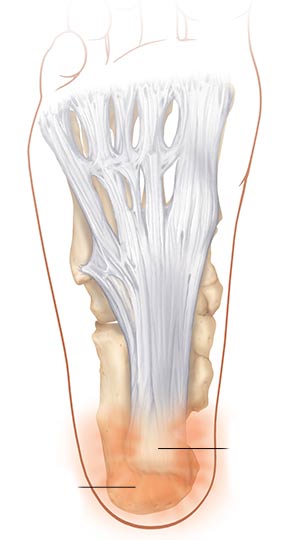

التهاب پلانتار یا غلاف کفپایی

التهاب پلانتار زمانی روی میدهد که تاندون غلاف کفپایی که پاشنه پا را به انگشتان متصل میکند دچار التهاب و تورم شده باشد. این عارضه به علت ساختار پا ایجاد میگردد. افراد مبتلا به عارضه صافی کف پا یا قوس زیاد کف پا بیشتر در معرض خطر ابتلا به التهاب پلانتار هستند. درد پاشنه پا مخصوصاً در صبح از مشخصههای بارز عارضه التهاب پلانتار میباشد.